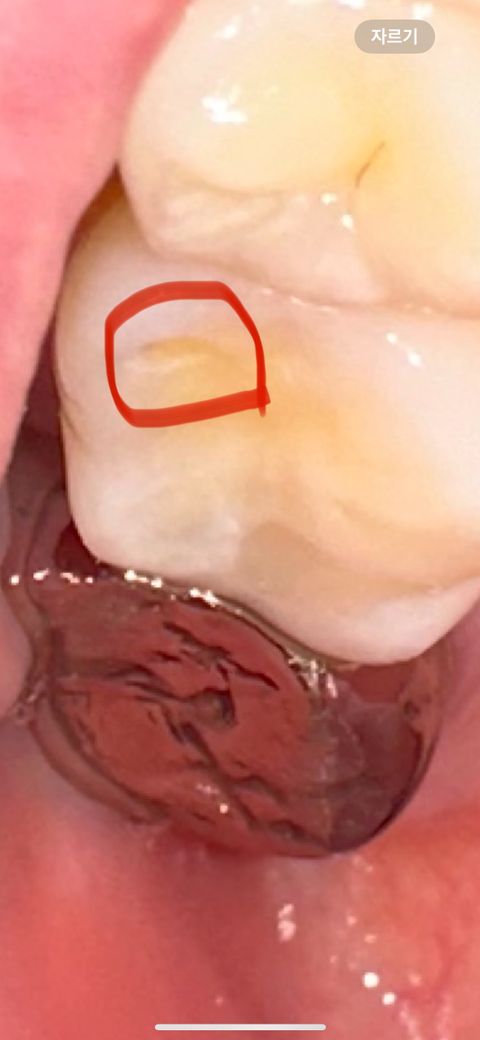

구멍 파임이 치료가 시급한가요? ㅠㅠ

원래는 아예 저런 파임이 없었지만 생긴지 한 6개월 정도 된거같아요 근데 시리지도 않고 아프지도 않습니다 구멍이 갈수록 조금씩 더 커짐? 더 파임? 그런건 좀 느껴져요 치료가 급한걸까요? 꼭 치료 받아야하는건가요?

• 1번 째 사진

• 사진으로 보이는 구멍은 마모로 인해서 생긴 구멍으로 보입니다. 크게 문제가 되진 않을 것으로 생각되기 때문에 시린 증상이 심하지 않다면 굳이 충전을 하지 않으셔도 됩니다.

치아에 마모가 생겼다면 그만큼 강한 힘이 치아에 강하고 있다는 의미이기 때문에 치아에 가해지는 힘을 줄여주는 것이 좋습니다.

• 해당 부위가 점점 넓어지는 느낌이 든다면 치과 방문 후 치료를 하는 것이 좋습니다. 지금과 같은 상태가 계속 지속되면 음식물이 해당 부위로 많이 저류하게 되어 충치로 이어질 가능성이 있습니다. 따라서 치과 방문 후 치료를 하는 것을 권해드립니다.

• 안녕하세요 치과의사 김철진입니다. 저정도는 치아가 교합되면서 자연스럽게 생긴 교모라 특별히 불편하지 않으면 치료를 하지 않으셔도 될것같습니다

• 충치로 인한 것은 아닌 것 같고 단순 마모같습니다 치료가 급하진 않고 마모, 교모를 유발하는 습관에 대한 개선이 필요합니다 보통 이갈이, 이악물기 등에 의해 마모가 유발됩니다